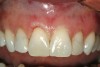

Figure 1  Preoperatively, the patient‚Äôs smile showed a full gingival display and asymmetrical gingival levels in the maxillary anterior region. Although the ‚Äúgummy smile‚Äù may not be able to be eliminated completely, better symmetry of the tissue levels was one of the goals of treatment.

Figure 1